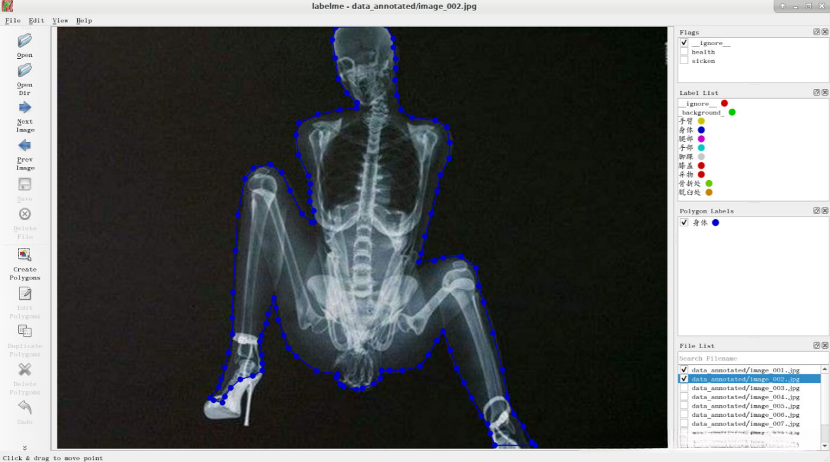

10.点击“Next Image”,将图像中人是否是健康的,无法判定时选择“ignore ”。

将图像中人体标注出来并选择相应的label。